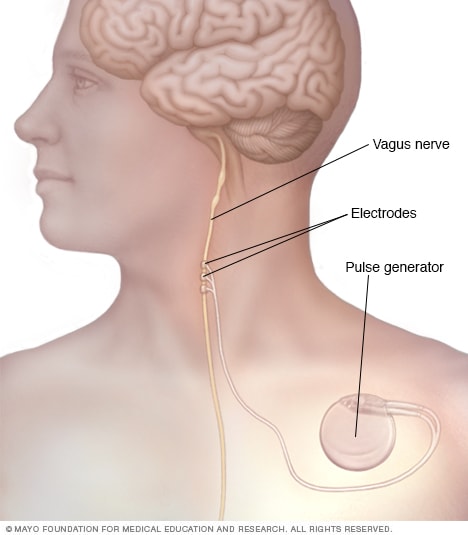

Vagus nerve stimulation. In vagus nerve stimulation, doctors implant a device called a vagus nerve stimulator underneath the skin of your chest, similar to a heart pacemaker. Wires from the stimulator are connected to the vagus nerve in your neck.

The battery-powered device sends bursts of electrical energy through the vagus nerve and to your brain. It's not clear how this inhibits seizures, but the device can usually reduce seizures by 20 to 40 percent.

Most people still need to take anti-epileptic medication, although some people may be able to lower their medication dose. You may experience side effects from vagus nerve stimulation, such as throat pain, hoarse voice, shortness of breath or coughing.